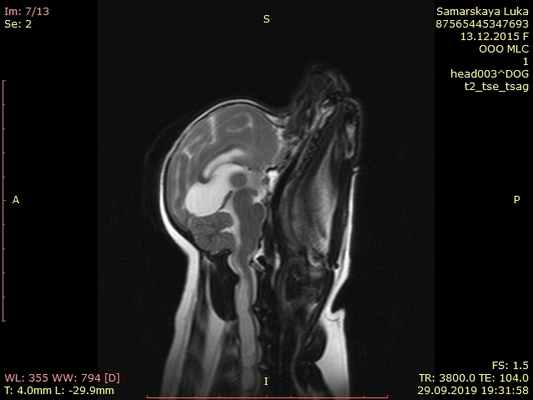

МРТ исследование пациентов с атланто-аксиальной сублюксацией

МРТ обеспечивает превосходное разрешение при исследовании нервной паренхимы и позволяет выявить другие патологии мозга, такие как дорсальную компрессию С1-С2, атланто-окципитальный оверлепинг, Киари и прочее.

Той терьер с атланто-аксиальной нестабильностью

На мрт исследовании нашего пациента – здесь представлена сагитальная Т2 взвешенная последовательность, определяется смещение аксиального позвонка в дорсальном направлении по отношению к атланту, дислокация дорсальной дужки атланта к задней черепной ямке с тяжелой компрессией как мозжечка, так и спинного мозга.